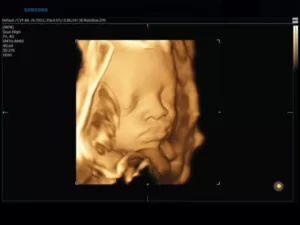

Режим 3D/4D

Технология объемного сканирования позволяет исследовать пространственное местонахождение объектов в различных проекциях в режиме «замораживания» (3D static) и реального времени (4D). Такая возможность достигается путем совмещения большого количества плоских двумерных изображений, зафиксированных с различных сторон. Наибольшее распространение эхография в 3D и 4D получила в акушерстве и гинекологии.

Для данного типа сканирования применяются объемные датчики. В зависимости от цели обследования излучатели в объемных насадках могут быть линейными, конвексными или фазированными.

66.jpg

Рис.7. Лицо плода в 3D-режиме (объемный датчик 1-8 МГц).